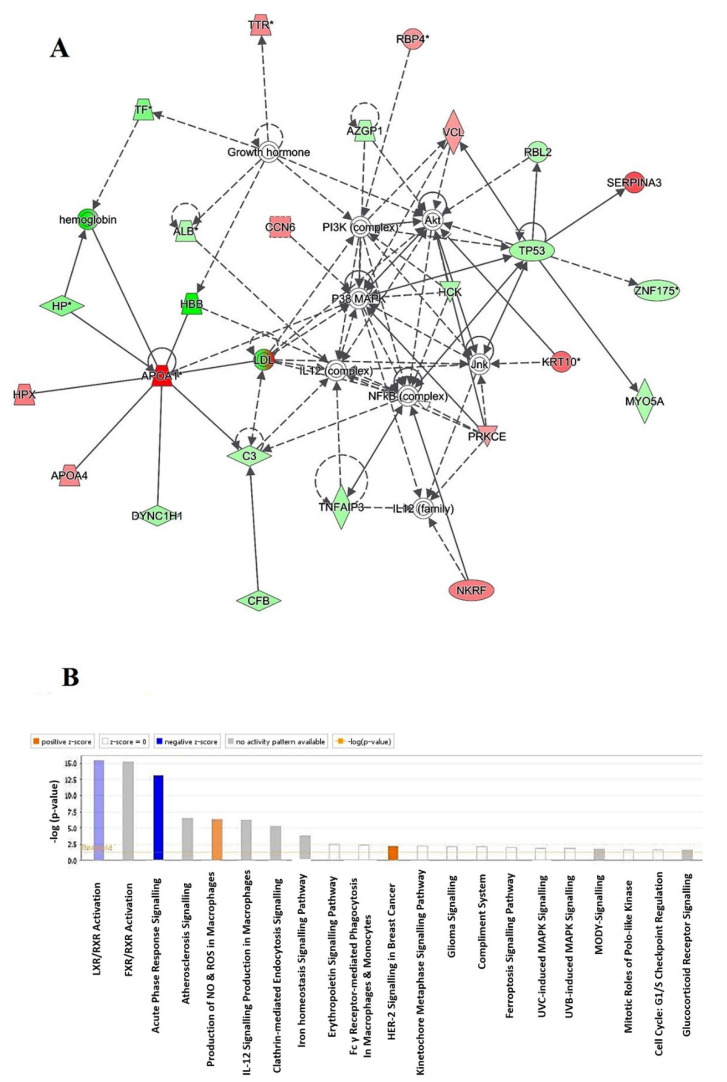

2.4. Protein–Protein Interaction Networks

Using Ingenuity Pathway Analysis (IPA), the protein–protein interaction analysis was completed for all 121 regulated proteins. The analysis demonstrated that 35 proteins interacted directly/indirectly via protein networks (Figure 5A). The software calculates the best fit score obtained from the input data set of proteins and the biological functions database in order to generate a protein–protein interactions network. The generated network is favorably enriched for proteins with extensive and specific interactions. The interacting proteins are characterized as nodes and their biological relationships as a line. Based on the resulted data, four interaction networks were recognized for the proteins exhibiting variance expression profiles. The highest scoring network (score = 52) (Figure 5, Supplementary Figure S1) incorporated 25 proteins. The proposed highest interaction network pathway was related to free radical scavenging, cellular compromise, and inflammatory response. Alone the top pathways are presented (Figure 5A). Canonical pathways that enriched in current dataset are presented in Figure 5B. The canonical pathways are sorted down to decreasing log (p-value) of enrichment. The most interesting enriched canonical pathways included liver X receptors/retinoid X receptor (LXR/RXR) activation (11% overlap, p-value: 3.7 × 10−16), farnesoid X receptors/retinoid X receptor activation (10.7% overlap, p-value: 5.78 × 10−16), acute phase response signaling (7.4% overlap, p-value: 7.15 × 10−14), atherosclerosis signaling (5.6% overlap, p-value: 3.87 × 10−7), and production of nitric oxide (NO) and reactive oxygen species (ROS) in macrophages (4.3% overlap, p-value: 4.24 × 10−7). More details about the identified canonical pathways are shown in supplementary files (Supplementary Figure S1).